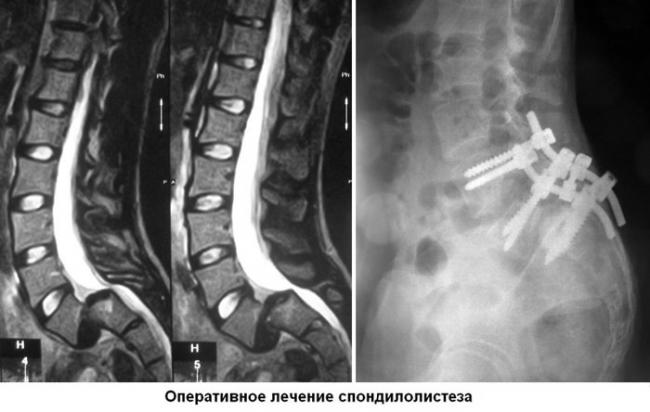

Оперативное вмешательство

К хирургической операции прибегают в том случае, если патология на 2 стадии и позднее. Чрезмерное смещение позвонка опасно сдавливанием спинного мозга, поэтому провести декомпрессию стоит как можно скорее. Вмешательство позволит также стабилизировать позвоночник.

Основным популярным способом является лапароскопия. Она отличается минимальной травматичностью и небольшими осложнениями после операции. Через небольшой разрез запускается зонд, который обеспечивает видеосъемку для полной видимости. В процессе не задеваются мягкие ткани, волокна мышц или связки, а значит кровотечение небольшое. После операции пациент может как можно скорее вернуться к нормальной жизни.

Пораженный позвонок замещается вентральной пластиной, или фиксируется винтами, замещается титановыми имплантами. Подбирается вид материала и подходящий вариант индивидуально, исходя из особенностей развития болезни.

Оперативное вмешательство назначается только при наличии показаний